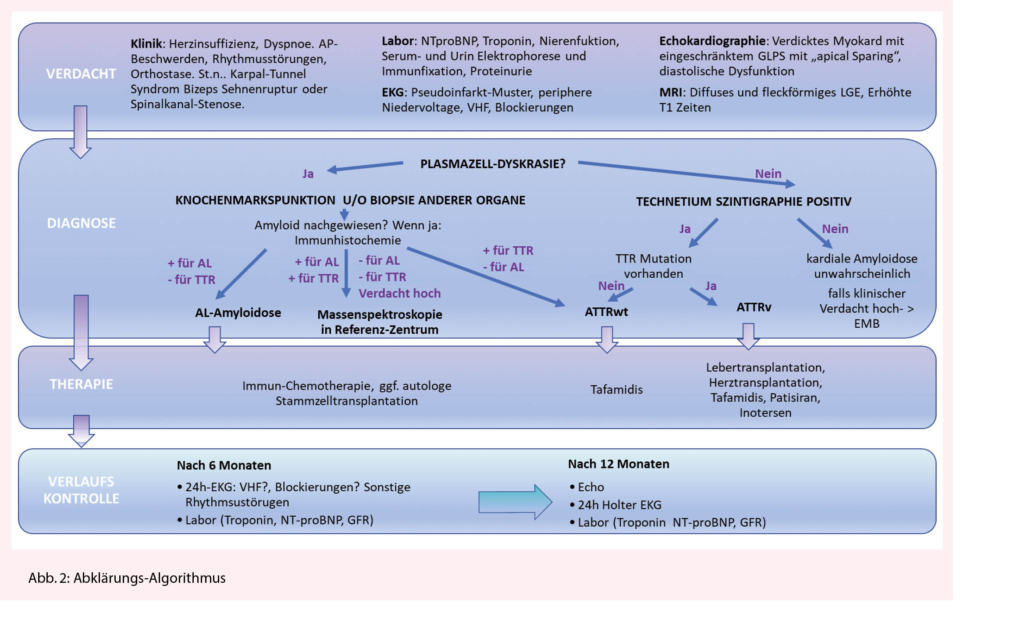

Bei Verdacht auf eine kardiale Amyloidose (Herzinsuffizienz-Beschwerden, typisches Echo oder MRI) sollten zuerst ausführliche Laboruntersuchungen inkl. kardiale Biomarker NT-pro BNP und Troponin (zur Abschätzung der Prognose) und eine Protein-Elektrophorese mit Immunfixation im Serum und Urin sowie Bestimmung der freien Leichtketten im Serum veranlasst werden. Letzteres ist entscheidend für die Unterscheidung zwischen AL und ATTR Amyloidose. Ein EKG sollte geschrieben werden, um die Frage nach Vorhofflimmern und Blockierungen zu beantworten. Die typischerweise beschriebene «low-voltage» findet sich eher bei der AL-Amyloidose, bei der ATTR ist dies jedoch nicht so häufig (ca. 22%), typischer ist dort ein Pseudoinfarktmuster (63%). Bei unauffälliger Immunfixation ist eine AL-Amyloidose praktisch ausgeschlossen (Abb. 2). In diesem Fall sollte eine Technetium Szintigraphie durchgeführt werden. Fällt diese positiv aus, gilt die Diagnose einer ATTR-Amyloidose als gesichert (4), jedoch kann nicht zwischen wtATTR und vATTR unterschieden werden, weswegen eine genetische Testung sinnvoll ist. Diese kann nach Einholen einer Kostengutsprache durch die Krankenkasse durchgeführt werden kann. An eine hereditäre Form sollte insbesondere dann gedacht werden, wenn neurologische Symptome wie Polyneuropathie vorhanden sind. Bei negativer Szintigraphie und persistierend hohem Verdacht auf eine kardiale Amyloidose, sollte eine Endmyokardbiopsie durchgeführt werden (5). Bei pathologischer Immunfixation und Verdacht auf eine kardiale Amyloidose ist die Situation etwas komplizierter, da die Diagnose mittels Biopsie und Nachweis von Amyloid gestellt werden muss. Normalerweise erfolgt bei pathologischer Immunfixation eine hämatologische Abklärung, gelegentlich gelingt der Nachweis von Amyloid schon in der Knochenmarksbiopsie (ca. 50%), ansonsten muss Amyloid an anderen Stellen (typischerweise Bauchfett, Speicheldrüsen, Endomyokard) gesucht und immunhistochemisch bestätigt werden, was gelegentlich herausfordernd sein kann (Abb. 2). Ein wichtiges Problem stellt die hohe Koinzidenz eines MGUS mit der wtATTR Amyloidose im fortgeschrittenen Alter dar.